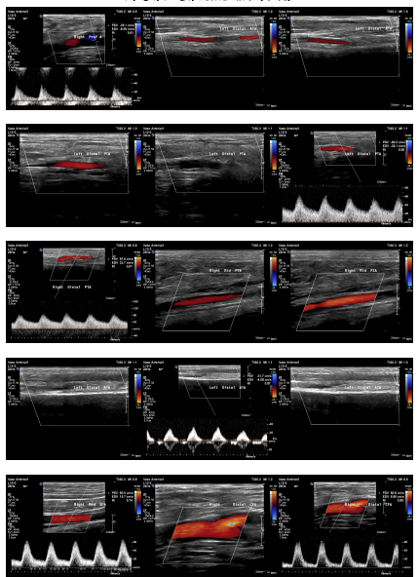

Relevant Test Results Prior to Catheterization

ABI measured on December 13, 2021, was 0.64on the right and 0.59 on the left. Duplex ultrasonography performed on August6, 2024, revealed monophasic flow in bilateral CFA, SFA, popliteal, ATA, andPTA arteries, favoring bilateral severe iliac artery disease. Subsequent CTangiography on November 15, 2024, demonstrated aortoiliac occlusive disease,without evidence of aneurysm or distal vessel obstruction. Laboratory databefore admission showed HbA1c 6.9% and LDL 76 mg/dL.

Diagnosticangiography revealed total occlusion of both common iliac arteries, while theexternal iliac arteries remained patent bilaterally. The lesions wereconsistent with aortoiliac occlusive disease (Leriche syndrome), and the distalflow was preserved via collateral circulation.